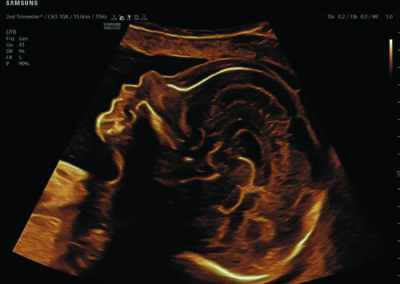

Comprehensive, advanced and expert MFM care for high-risk pregnancies